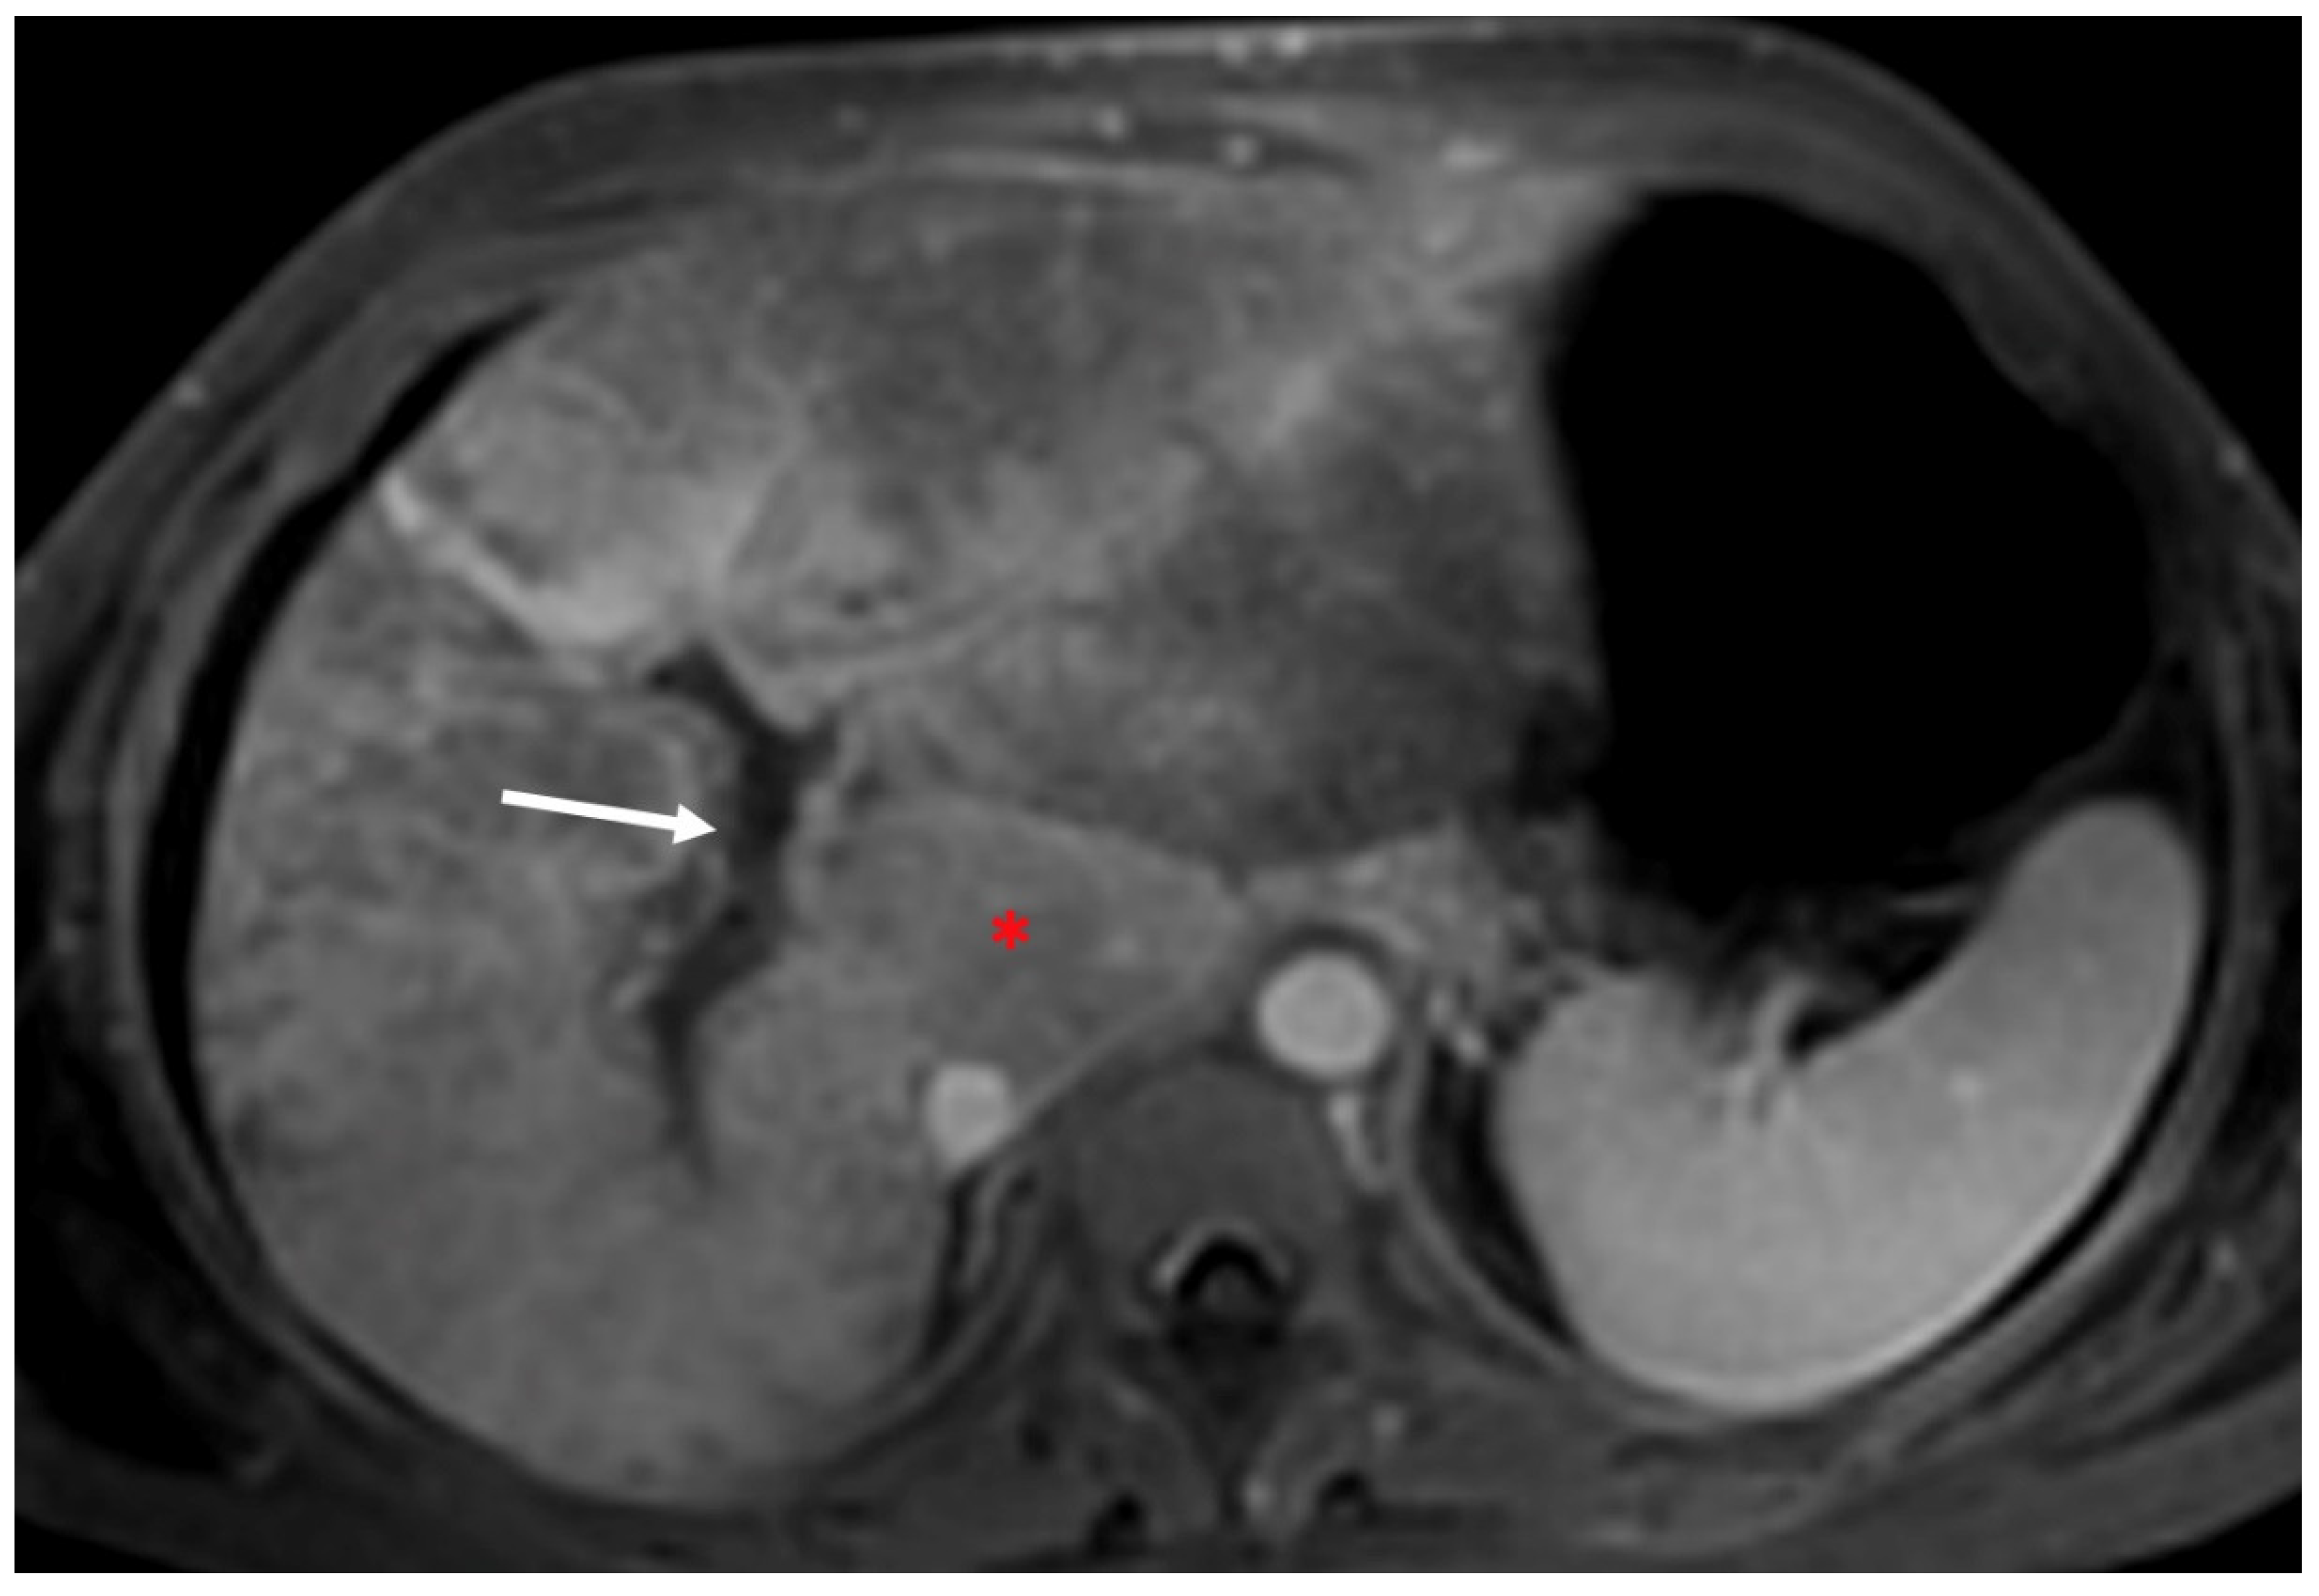

- Indirect signs: non-specific. They represent the consequences of long-standing hepatic venous impairment, including liver parenchymal changes with fibrosis and atrophy of involved segments and hypertrophy of unaffected territories (e.g., caudate lobe hypertrophy). On CT and MRI, centrilobular or sinusoidal congestion, represented as heterogeneous ”mosaic” enhancement after contrast media is also characteristic. Other signs include ascites, portal hypertension, and the presence of benign regenerative nodules, as well as hepatocellular carcinoma [6].

3.2. Computed Tomography and Magnetic Resonance: What to Look For

| MRI | Characterization of nodules (FNH-like nodules vs. HCC) T1-w decreased signal in hypoperfused regions, corresponding to high T2-w SI T2*-w flow void corresponding to thrombus. Hypointensity along the occluded vessels |